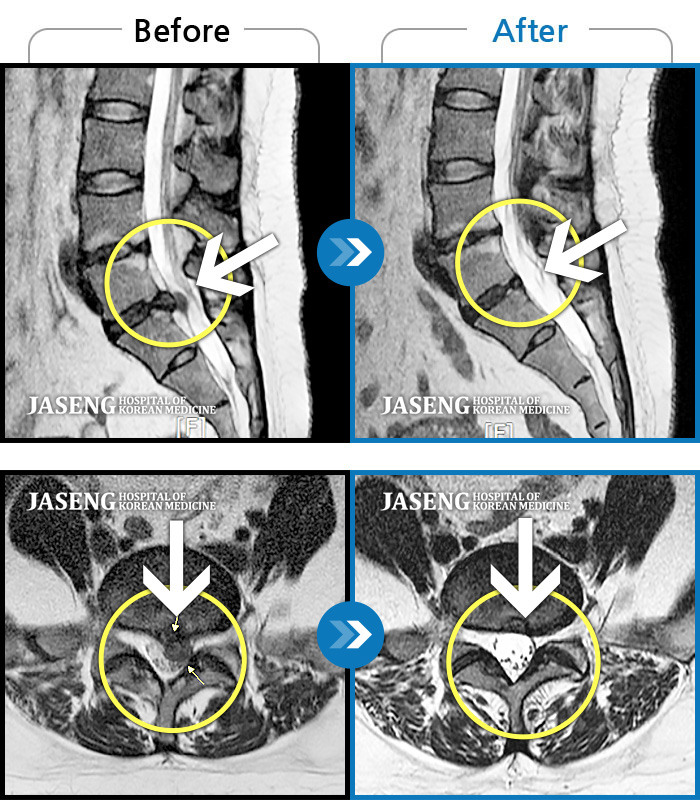

허리디스크

인천 · 조남훈 원장

좌측 허벅지와 종아리가 찌릿하고 묵직한 통증이 있어요.

촬영시기

2025.03.18 ~ 2025.07.22

2025.08.01